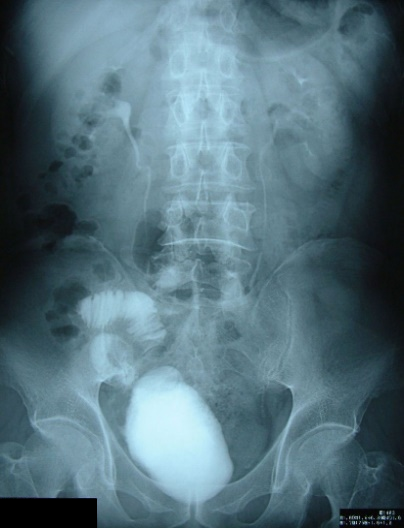

回腸代用膀胱造設術

残尿なく良好に排尿できます。